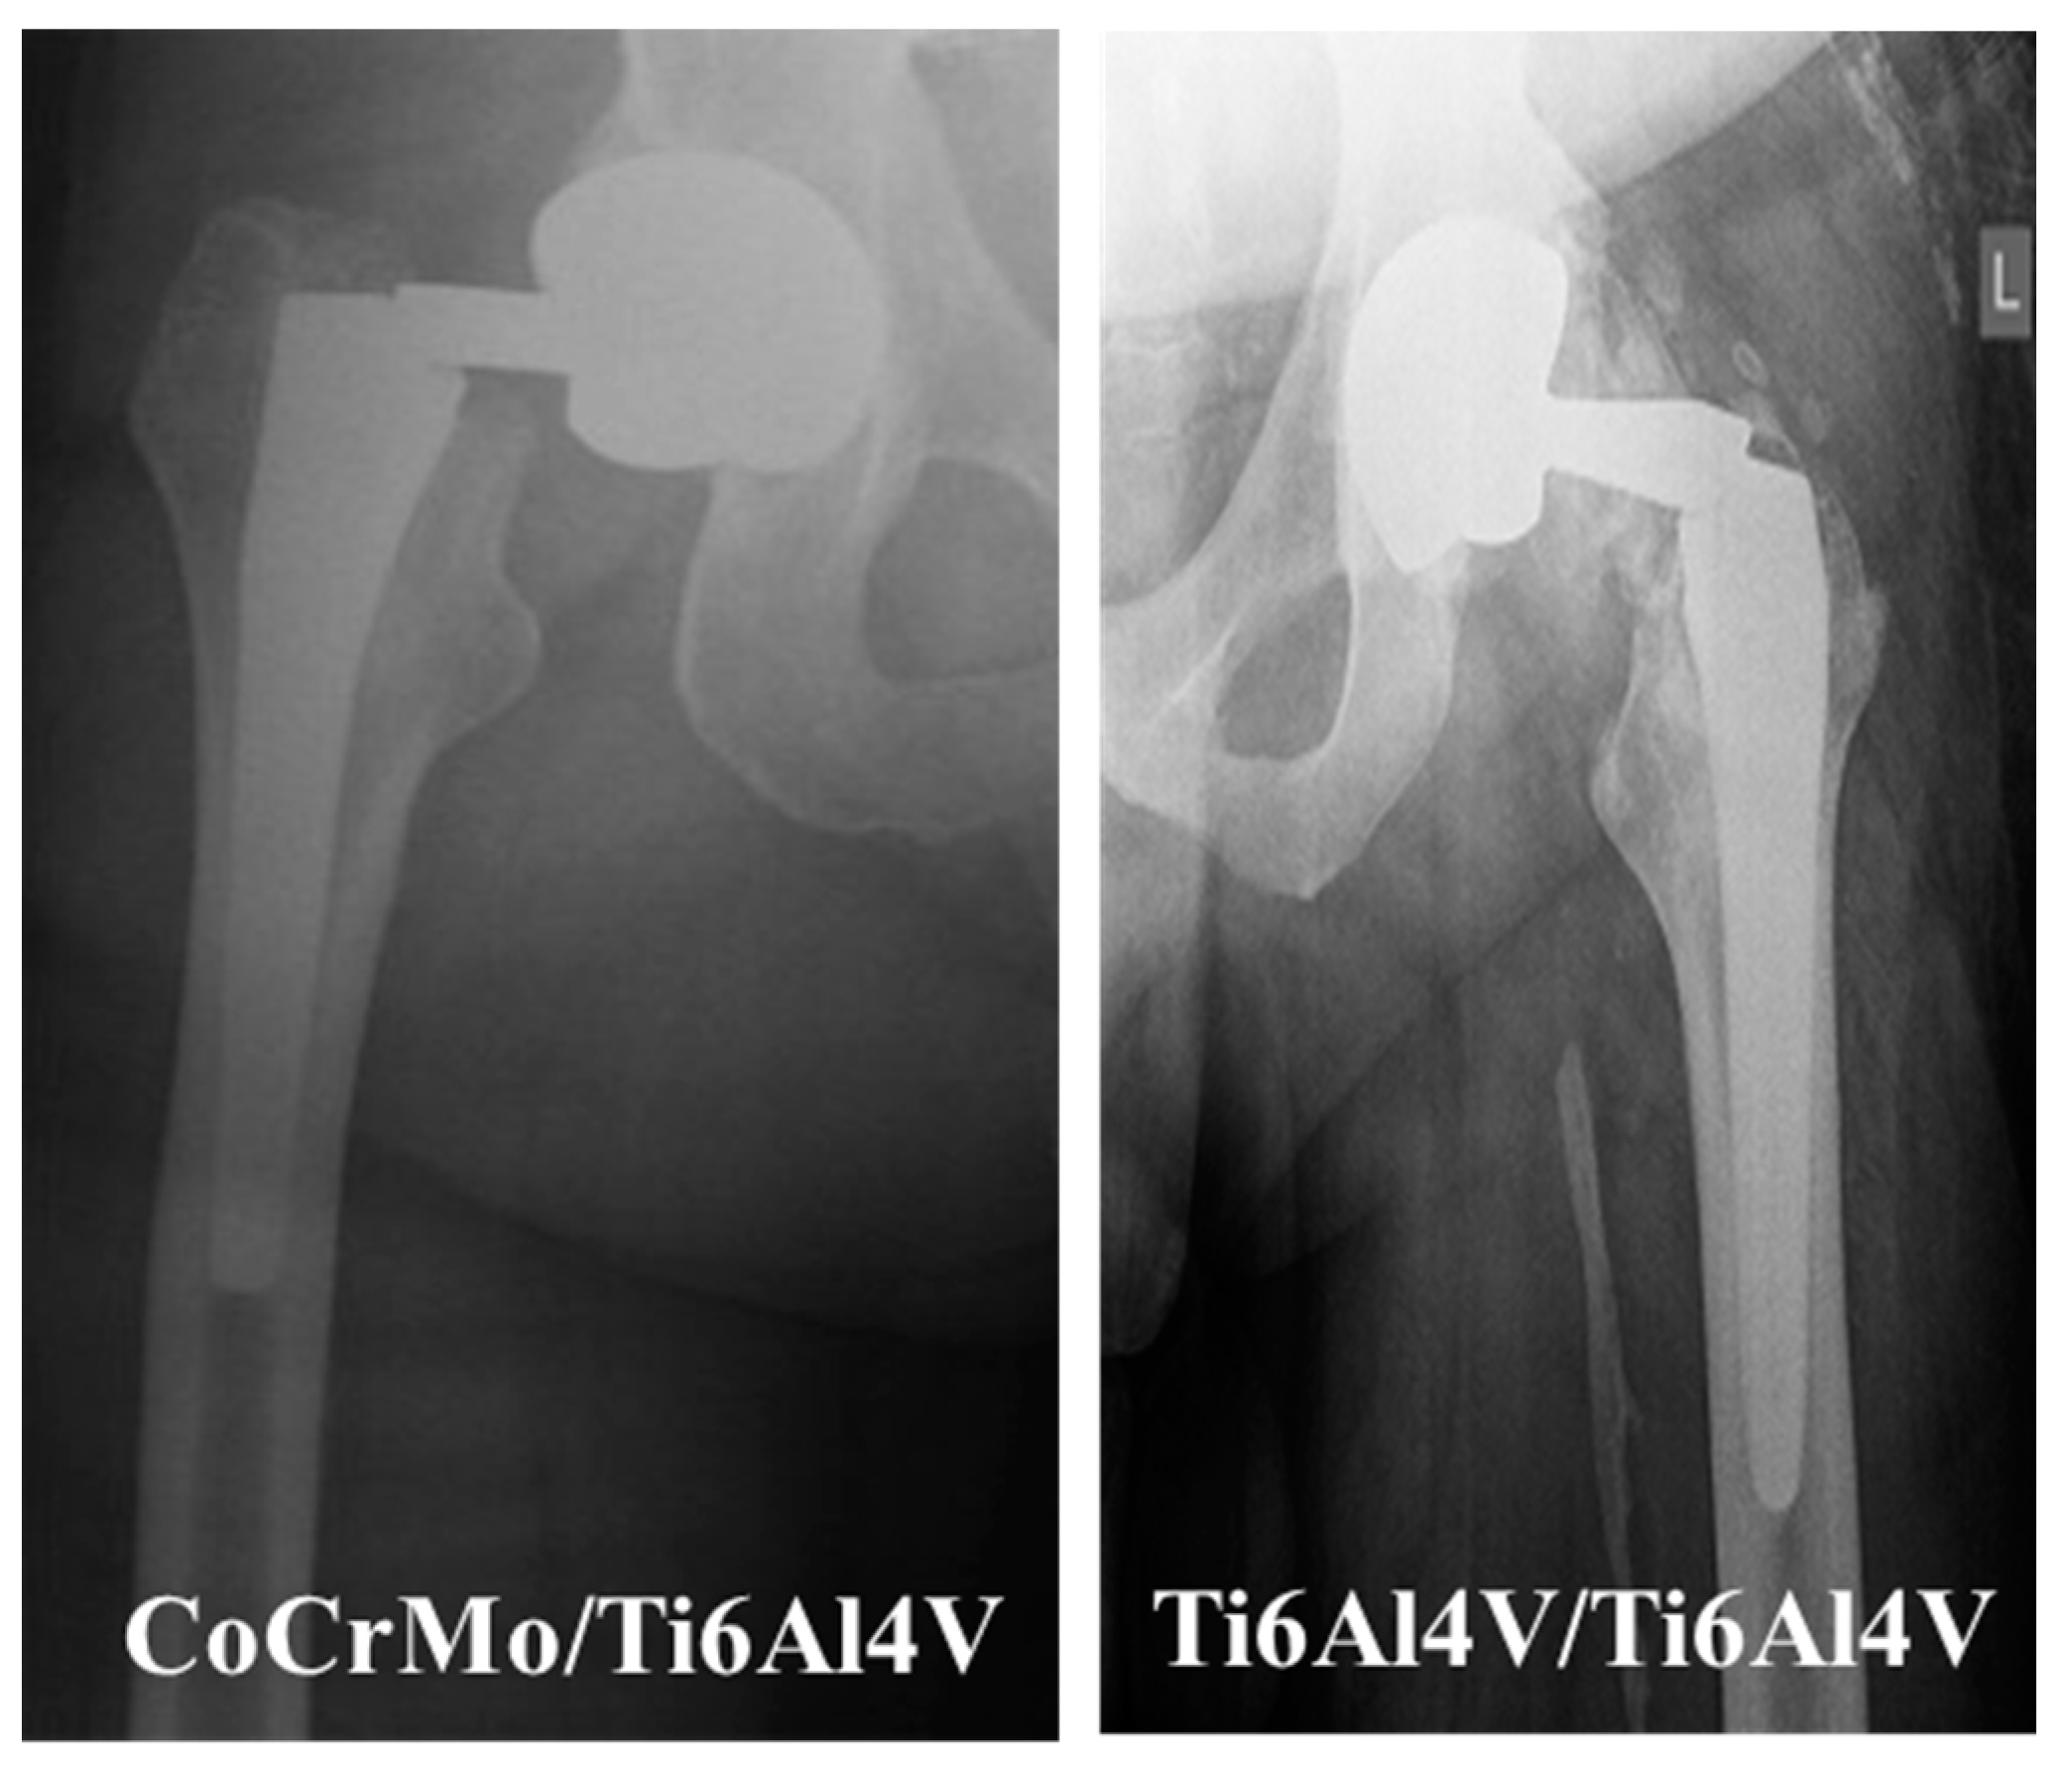

2.3.1. Modular Neck Stem Made of CoCrMo (Neck) and Ti6Al4V (Stem) Alloy

2.3.2. Modular Neck Stem Made of the Same Ti6Al4V (Neck) and Ti6Al4V (Stem) Alloy